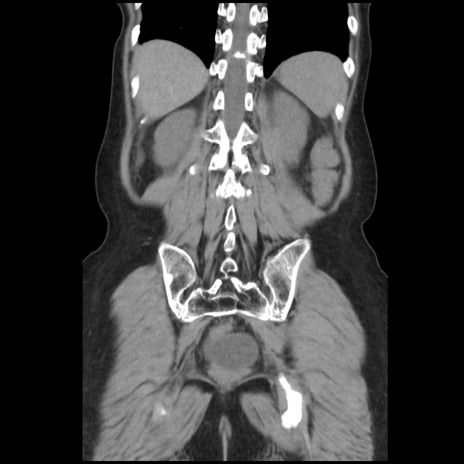

症例32(冠状断像)

【症例】40歳代 女性

【主訴】上腹部痛、嘔気・嘔吐

【現病歴】約9時間前頃から急に上腹部痛、嘔気、嘔吐が出現。改善しないため救急要請。

【既往歴】子宮頚癌(広汎子宮全摘術、放射線療法)、腸閉塞

【身体所見】腹部:平坦、軟、腸雑音亢進、上腹部を中心に腹部全体に圧痛あり。

【データ】WBC 8400、CRP 0.03